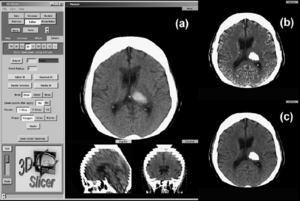

- 4.7 Comparison of the Tada Formula with Software Slicer: Precise and Low-Cost Method for Volume Assessment of Intracerebral Hematoma